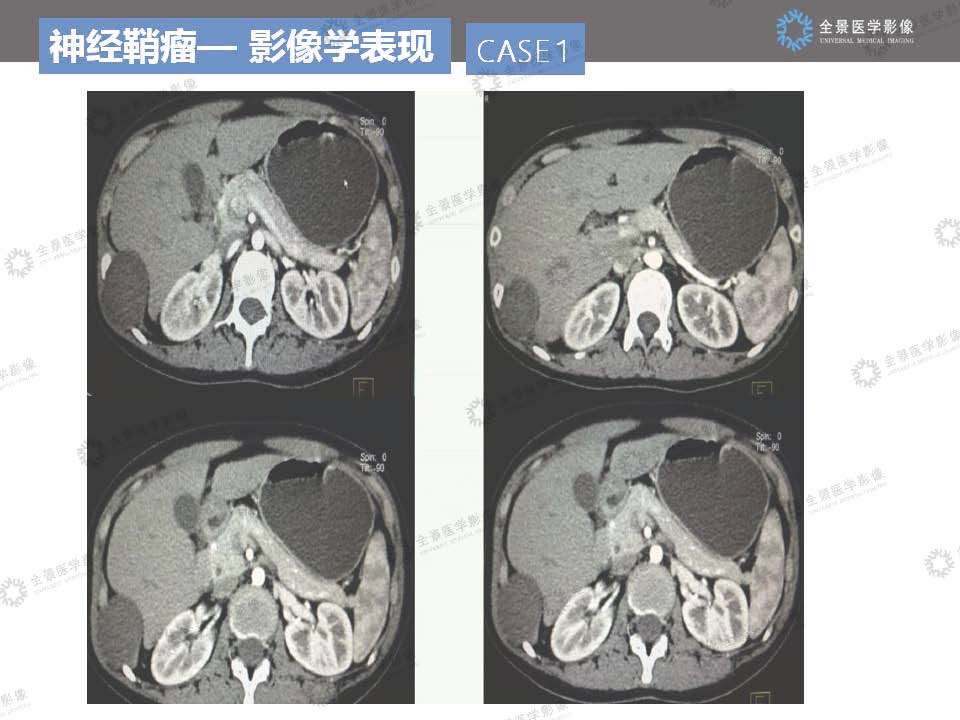

神经鞘瘤读片病例